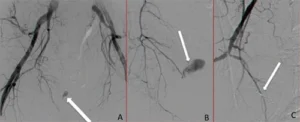

Arteriografia che mostra il flusso di contrasto extra-luminale e la sede della lesione arteriosa, evidenziata dalla freccia bianca

Figura A e B: arteriografia con stravaso extra-luminale di mezzo di contrasto, sede della emorragia (freccia bianca). Figura C: Arteriografia eseguita alla fine che dimostra chiusura del vaso che stava sanguinando. La freccia bianca indica il mezzo embolizzante usato (spirali).

Arteriografia finale che mostra la chiusura dell'arteria sanguinante tramite spirali embolizzanti e cessazione dell'emorragia